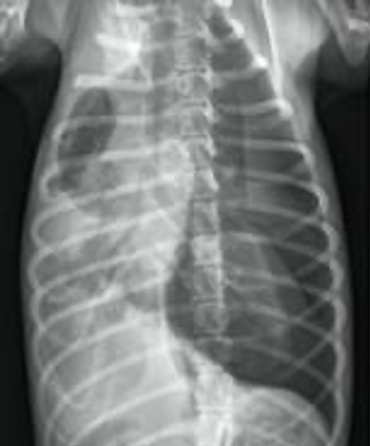

19

Q

What can you see in this lung ultrasound?

A

Pulmonary contusions (B-lines)